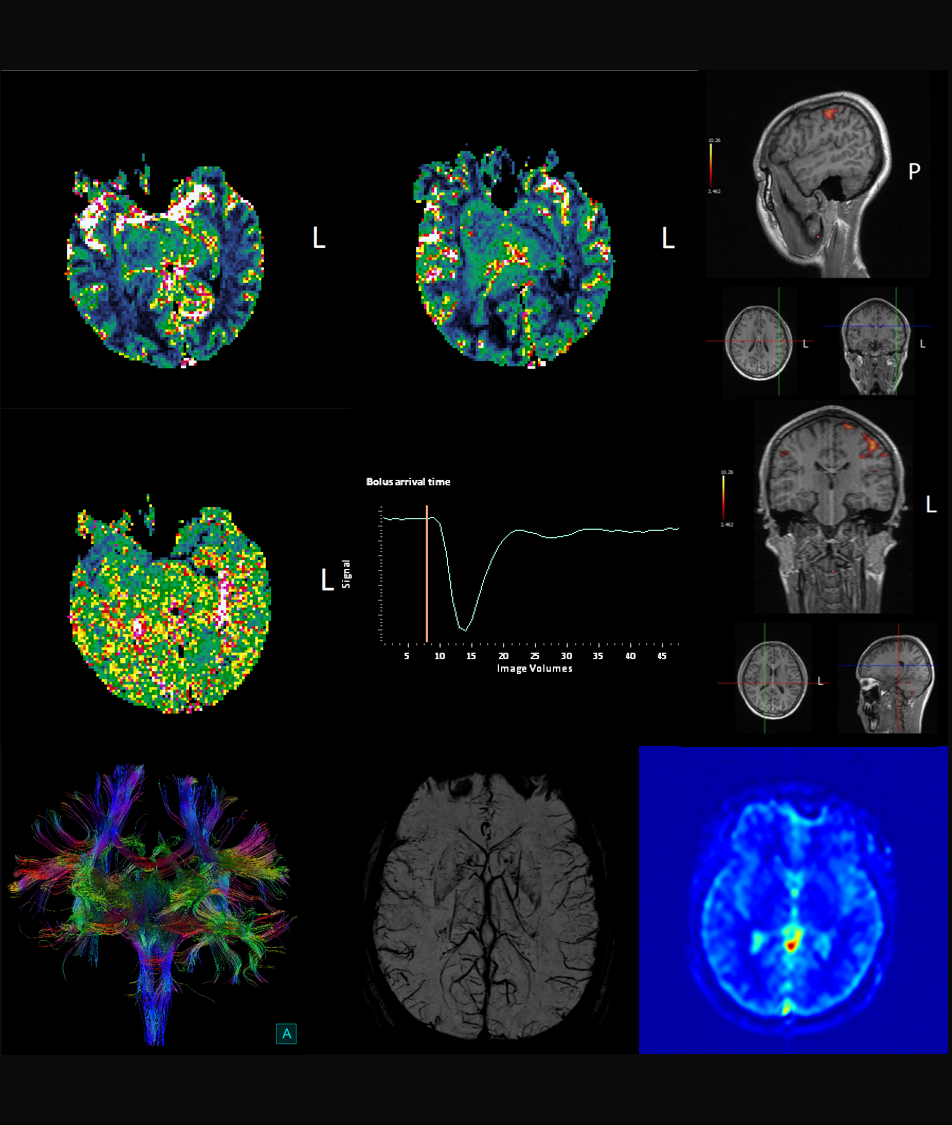

MR

ÖÐÊàÉñ¾­

ÖÐÊàÉñ¾­-¸ß¼¶ÁÙ´²Ó¦ÓÃ